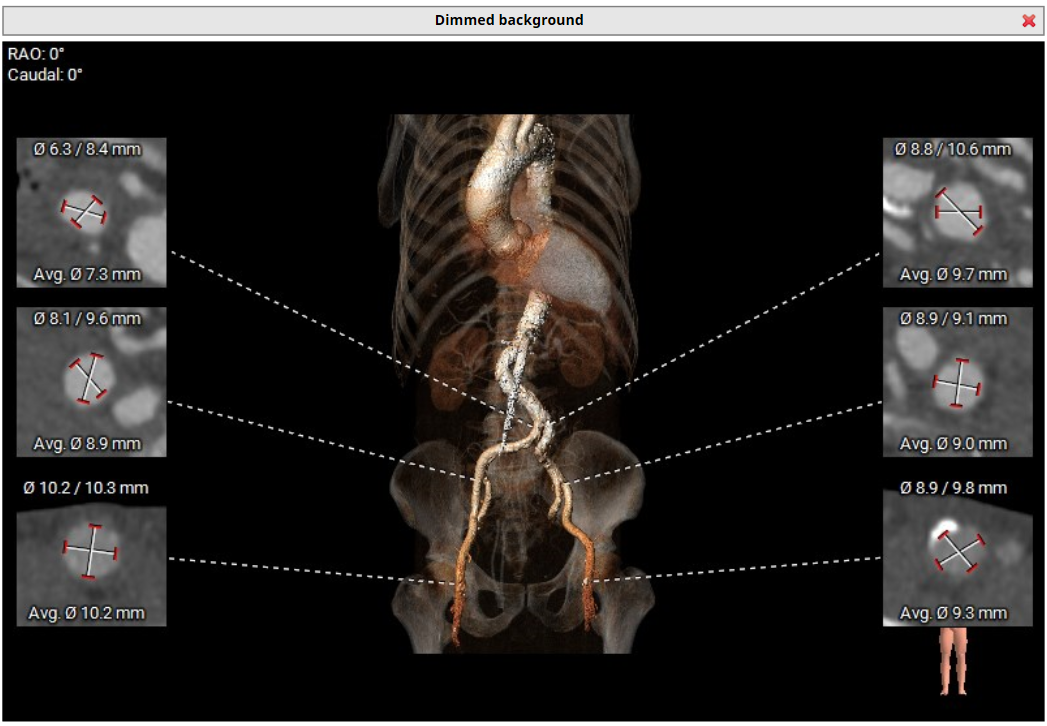

CT评估:三叶式主动脉瓣,无钙化,瓣环27.9mm,窦直径44-46mm。

入路解剖